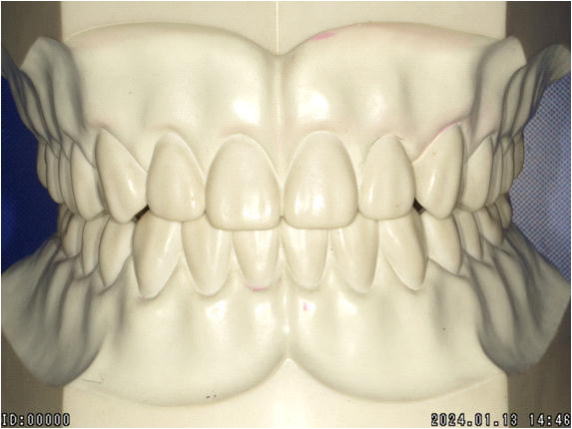

【正常な咬合関係】 |

正常な噛み合わせは、正中が合っており、左右ほぼ対称です。

前後の噛み合わせも平面的であるため、ズレることなくしっかり咬むことが出来るわけです。 |